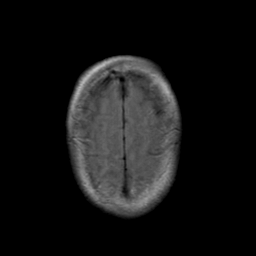

Stroke: proton density-weighted MR #2 -- Slice #21

[Home][Help][Clinical] Slice 21